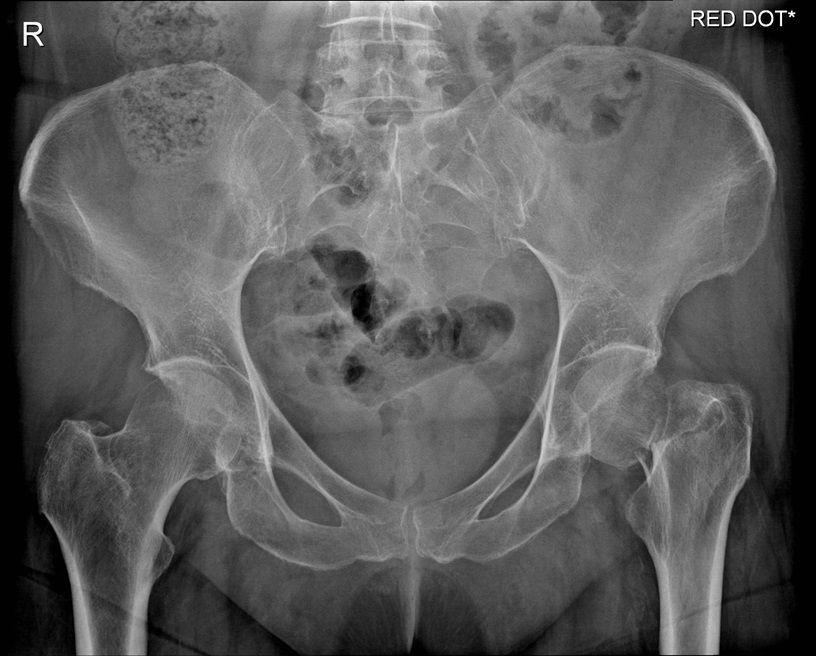

Question 2

Question

Which operation would you perform?

Answer

• THR

• Hemiarthroplasty